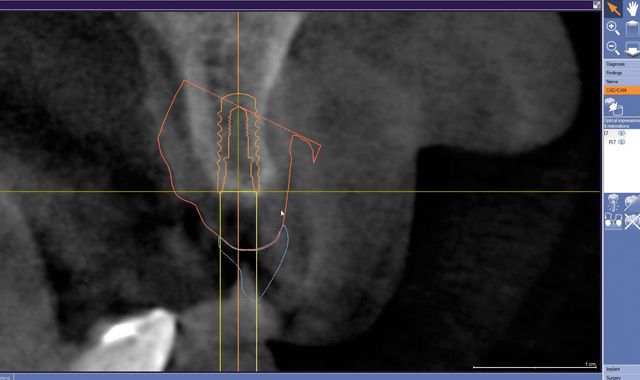

Fig. 09 A cross-sectional image showing the integrated CAD/CAM virtual restoration with the planned implant.

Fig. 10 A volumetric analysis of comprehensive implant planning.